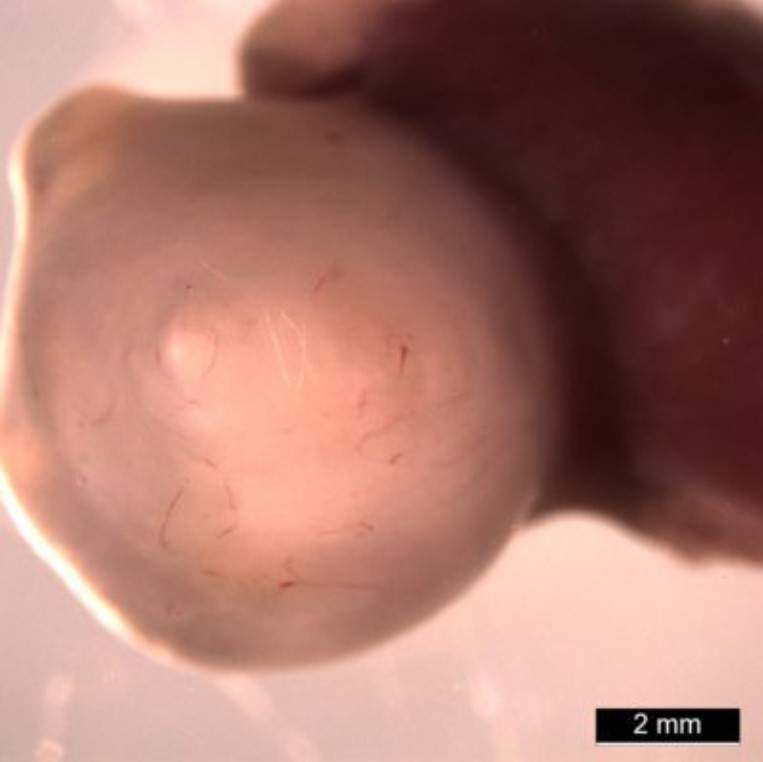

Для того, аби слідкувати за розвитком органоїду, науковці пересадили їх мишам. Завдяки припливу крові й більшого простору, шлунки виросли в тисячу разів більшими, ніж це зазвичай відбувається у клітинній культурі. І з’явилися риси, яких раніше не вдавалося отримати.

Органоїд шлунка 10-тижневого віку, який росте всередині миші /Фото Медичний центр дитячої лікарні Цинциннаті